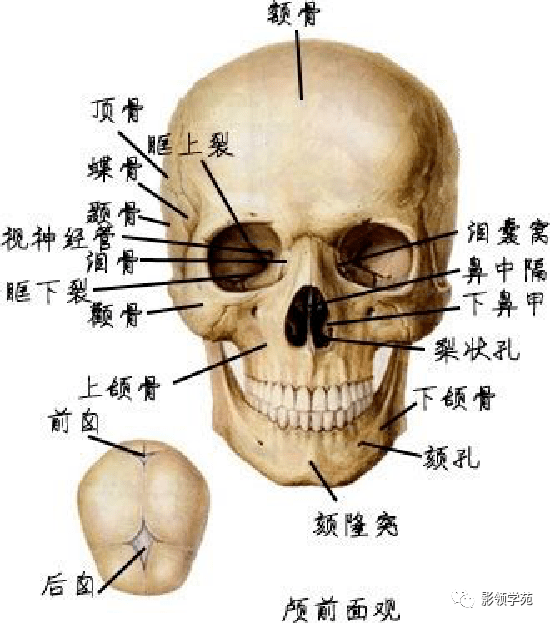

骨骼系统

骨骼系统